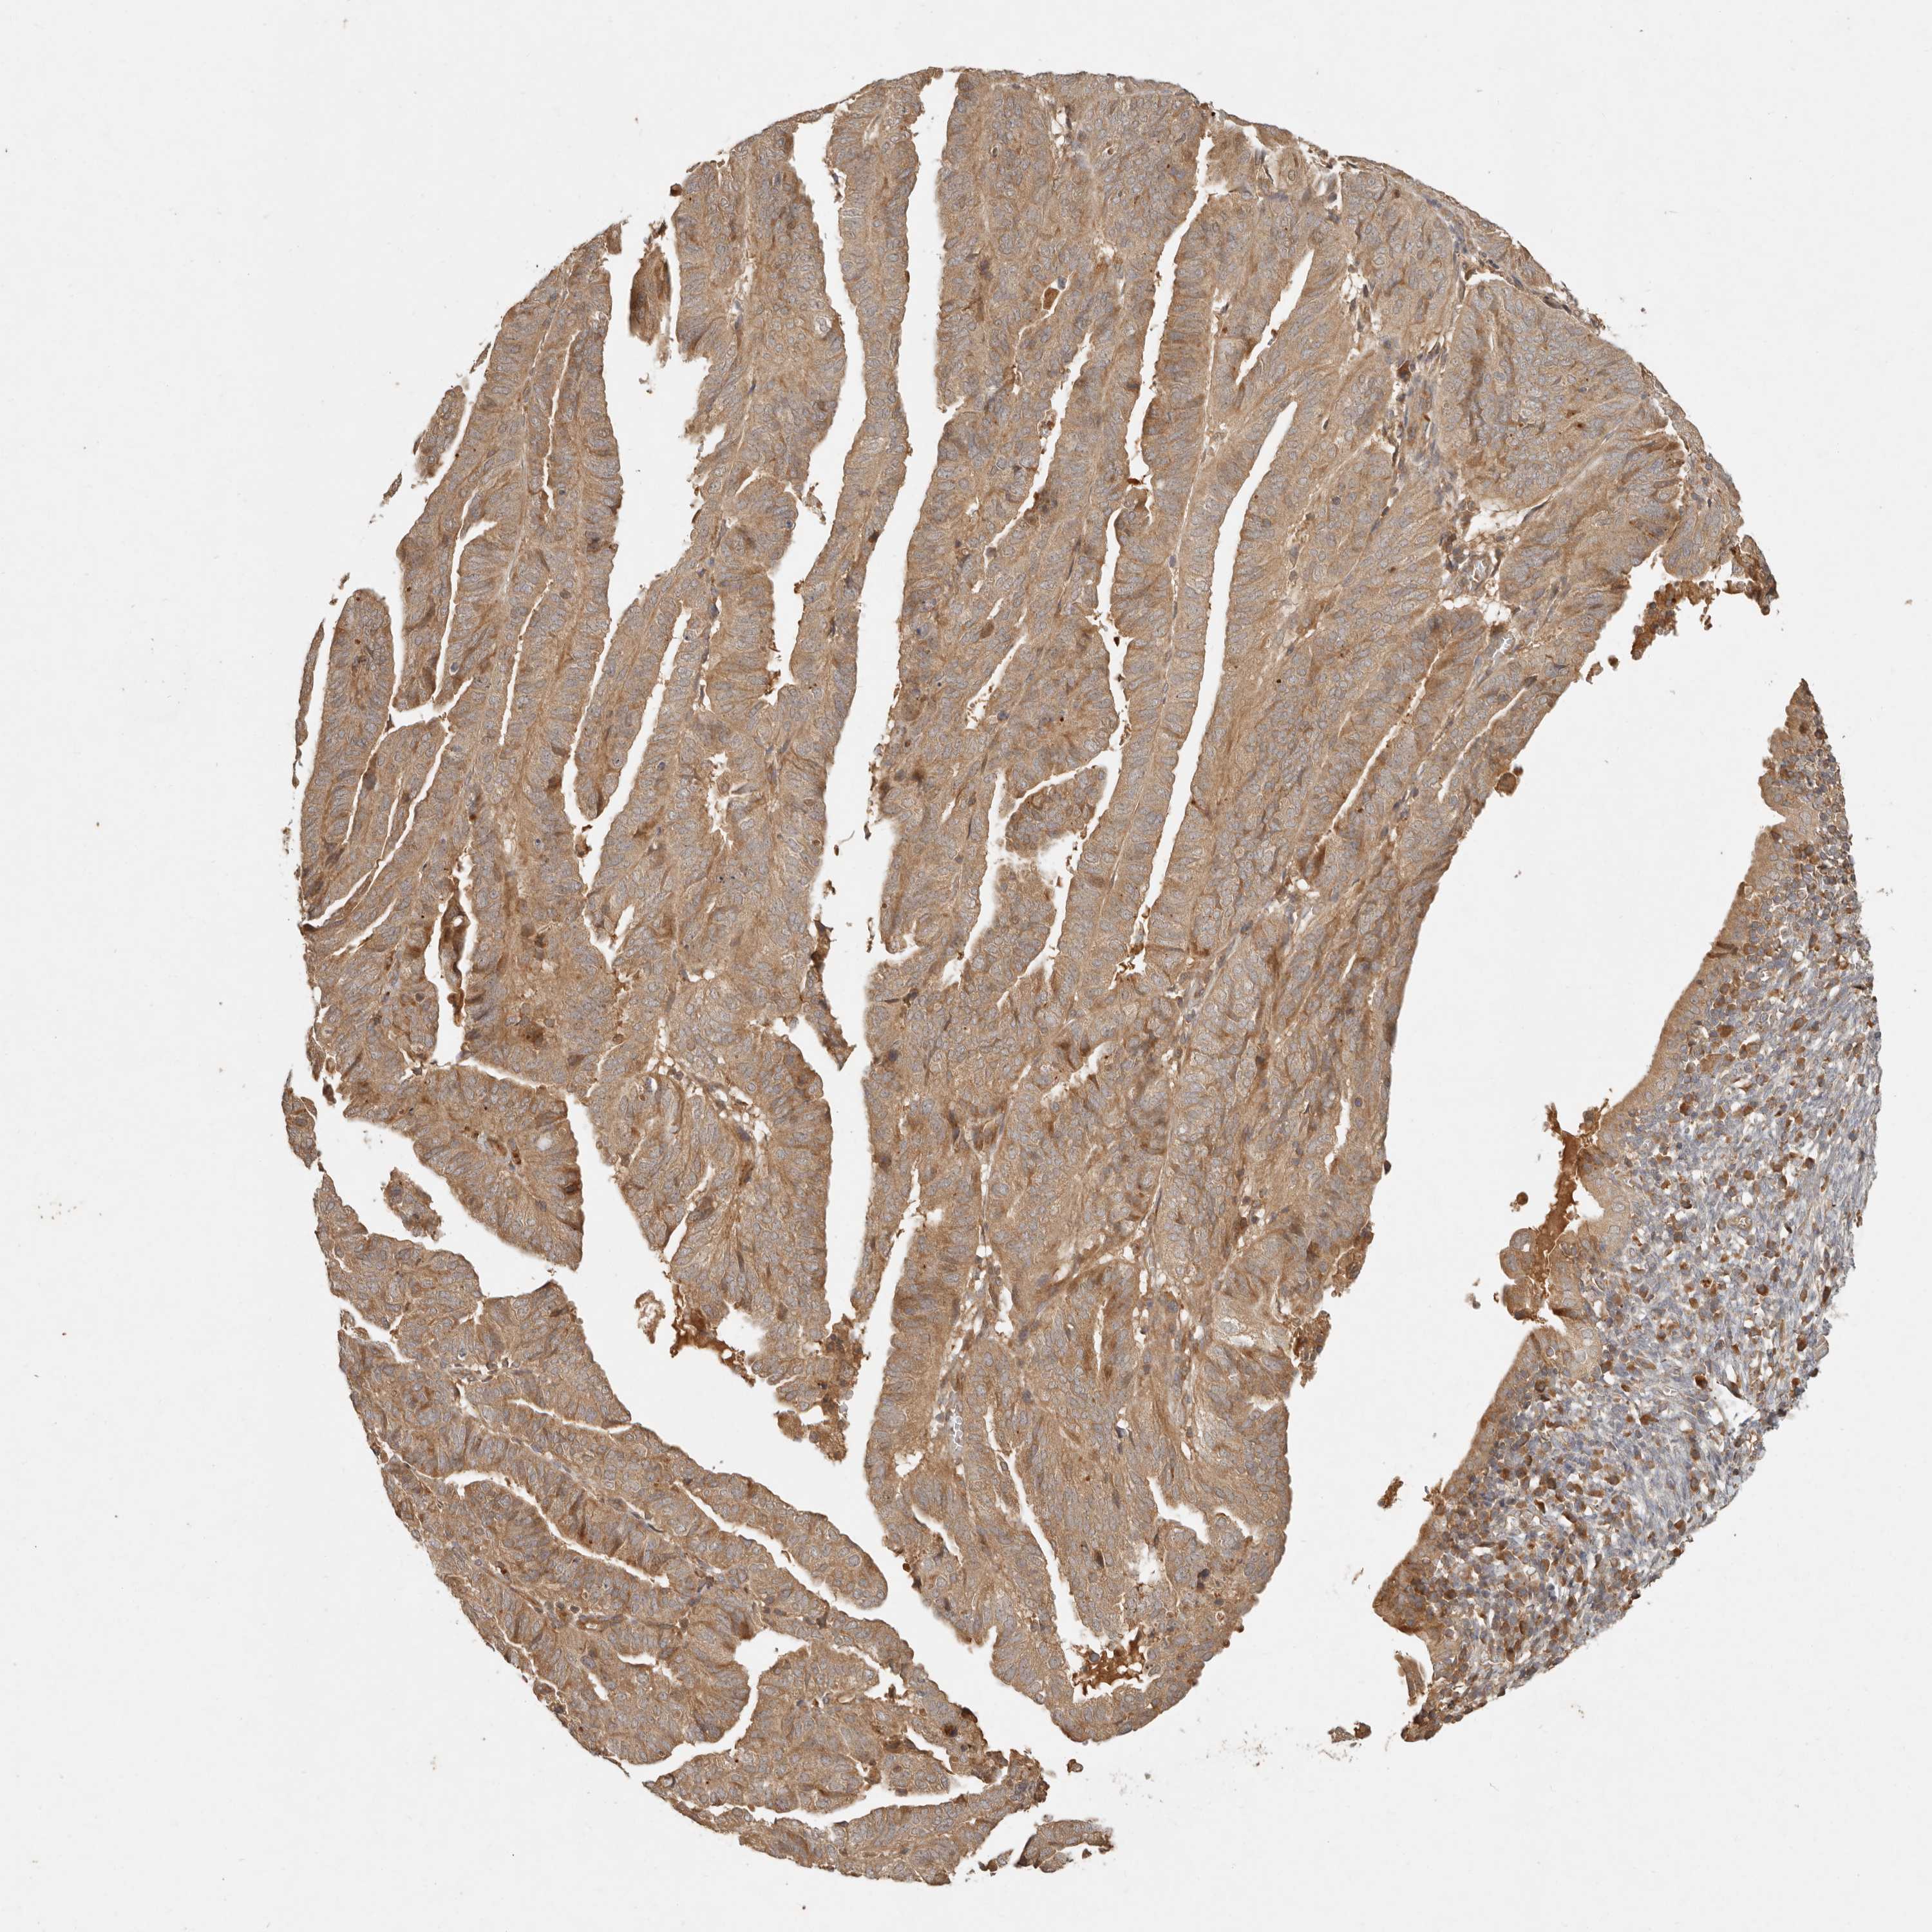

ENDOMETRIAL CANCER - Protein expressioni

A mouse-over function shows sample information and annotation data. Click on an image to view it in a full screen mode. Samples can be filtered based on level of antibody staining by selecting one or several of the following categories: high, medium, low and not detected. The assay and annotation is described here.

Note that samples used for immunohistochemistry by the Human Protein Atlas do not correspond to samples in the TCGA dataset.

Antibody stainingi

Antibody staining in the annotated cell types in the current human tissue is reported as not detected, low, medium, or high, based on conventional immunohistochemistry profiling in selected tissues. This score is based on the combination of the staining intensity and fraction of stained cells.

Each image is clickable and will lead to virtual microscopy that enables deeper exploration of all samples and also displays staining intensity scores, fraction scores and subcellular localization as well as patient and tissue information for each sample.

Antibody HPA029511

Staining

High

Medium

Low

Not detected

Intensity

Strong

Moderate

Weak

Negative

Quantity

>75%

75%-25%

<25%

None

Location

Nuclear

Cytoplasmic/membranous

Cytoplasmic/membranous,nuclear

Adenocarcinoma, NOS

Adenocarcinoma, metastatic, NOS